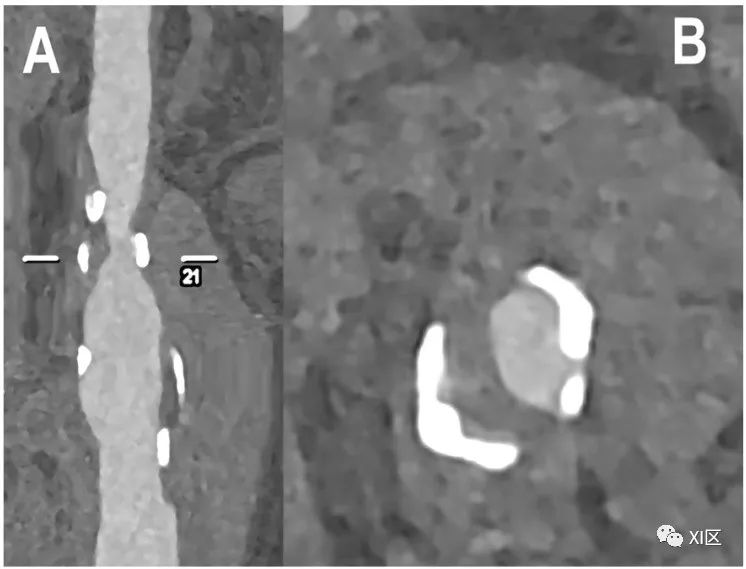

颈动脉分叉处的PCCT血管造影:轻度钙化动脉粥样硬化。PCCT血管造影显示超高清(源数据集;矩阵1024×1024;层厚/增量0.2/0.1mm;体素100 μm;卷积核Bv60;辐射剂量与使用第三代双源CT的同等颈动脉CT血管造影相当)颈动脉分叉处动脉壁增厚,近端颈内动脉处有轻度灶性钙化斑块(箭头所指)。

颈动脉分叉的PCCT血管造影:轻度非钙化动脉粥样硬化。PCCT血管造影显示了超高清(源数据集;矩阵1024×1024;层厚/增量0.2/0.1mm;体素100 μm;卷积核Bv60;辐射剂量与使用第三代双源CT进行的同等颈动脉血管造影相当)颈动脉分叉的纵向CPR成像,动脉壁有轻度弥漫性非钙化动脉粥样硬化。

颈动脉分叉的PCCT血管造影:中度混合性和钙化性动脉粥样硬化。PCCT血管造影显示了2个超高清(源数据集;矩阵1024×1024;层厚/增量0.2/0.1mm;体素100 μm;卷积核Bv60;辐射剂量与使用第三代双源CT进行颈动脉血管造影的同等剂量相当)颈动脉分叉处有严重钙化的动脉粥样硬化斑块((A);纵向和轴向视图)和中度/中度混合/钙化斑块((B);纵向和轴向视图)。值得注意的是,(A)中斑块的大块钙化完全分布在动脉壁内,不影响最终管腔狭窄的观察和量化。

颈动脉分叉处的PCCT血管造影:严重混合性动脉粥样硬化。PCCT血管造影显示超高清(源数据集;矩阵1024×1024;层厚/增量0.2/0.1mm;体素100 μm;卷积核Bv60;辐射剂量与使用第三代双源CT的同等颈动脉血管造影相当)颈动脉分叉处有严重的混合性动脉粥样硬化斑块((A):纵向视图;(B):轴向视图)。值得注意的是,无论是相对于剩余的非钙化部分,还是相对于管腔定义,斑块的大块钙化都非常清晰。需要强调的是,成分分析并不局限于原子成分,有证据表明PCCT可进一步用于更好地评估组织成分,神经血管领域以外的其他目标也证明了这一点:例如,骨小梁微结构分析、肾结石的检测和特征描述、乳腺组织特征描述以及痛风中晶体沉积的检测、分化和量化。